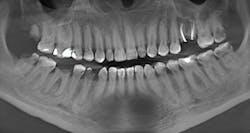

Case review: This 35-year-old female was diagnosed with Sjögren’s syndrome four years ago. She is a cigarette smoker and drinks multiple sodas per day. Her daily oral hygiene is marginal (figures 3–5).

Treatment objectives: Restore or replace all teeth to achieve full function and a natural, healthy-looking smile with a solution that is fixed and will last over the long term (20-plus years).

Today, more than ever, patients expect and hope their dental restoration will solve what has historically been a lifetime cycle of dental problems and expense. In this case, a straightforward, conventional restorative treatment plan that focuses on restoring the patient’s natural teeth may not make the most sense long term. After comparing both restorative paths, the full-arch implant option would likely prove to have a better prognosis, lower cost, and require much less time and fewer appointments.